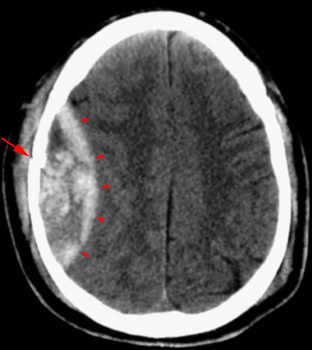

What causes a subdural hematoma?

What does it look like on an x-ray?

Bleeding of bridging veins resulting in blood gathering between the inner layer of the dura mater and the arachnoid mater (subdural space). May be due to blow to head that jerks brain inside cranium (i.e. hitting windshield in car accident).

Crescent shaped hematoma on side of brain